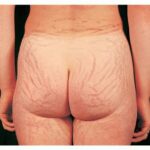

During puberty, striae appear in areas where there is a rapid increase in size. In girls, the most common sites are the breasts, thighs, hips, and buttocks, whereas in boys, they are seen on the shoulders, lumbosacral region, and thighs. Other less common sites include the abdomen, upper arms, neck, and axillae.

Striae are usually multiple, symmetric, well-defined linear atrophic lesions that follow the lines of cleavage. Initially, striae appear as red-to-violaceous elevated lines (striae rubra) . Over time, the color gradually fades, and the lesions become atrophic, with the skin surface exhibiting a fine, white, wrinkled appearance (striae alba). The striae can measure several centimeters in length and a few millimeters to a few centimeters in width. The striae associated with systemic corticosteroid therapy and Cushing syndrome can be larger and more widely distributed.